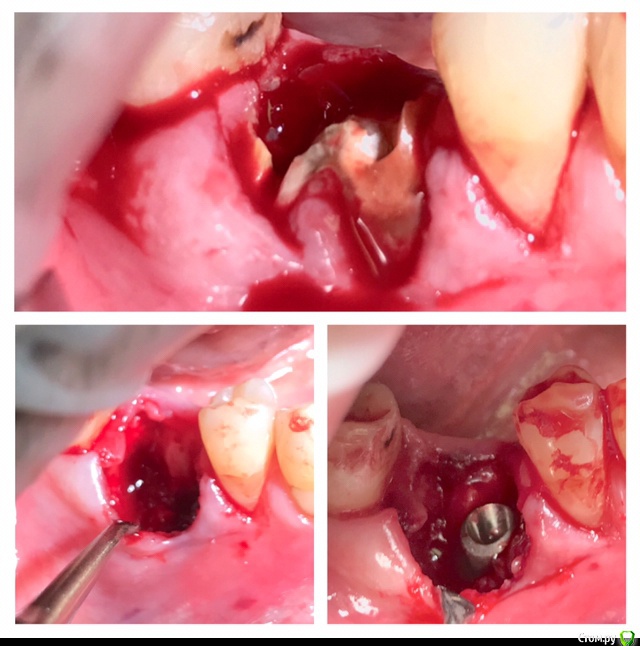

колесников Опубликовано 22 апреля, 2019 Поделиться Опубликовано 22 апреля, 2019 (изменено) И снова профайл спасает жизнь (облегчает жизнь имплантолога)Стандартная ситуация:36 периодонтит в стадии обострения с грануляциями,эксудацией,резорбцией компактной пластинки,дефицитом прикреплённой слизистой вестибулярного. Одна хирургия. Ноябрь 2018. Удаление,кюретаж,имплант Astra tech profile 4.5x9 под заглушку,торк около нуля. Вестибулярного сст,консервация графтом Sureoss 0,5 чипс с APRF,закрытие шайбой по Ноймайеру. Через неделю шайба несостоятельна-удалена. Пациентка созрела на удаление 37го. Выполнена декоронация в связи с отъездом пациентки,далее через 2 недели удаление и имплантация 37го. Промежуточный осмотр в январе. В марте установлены формирователи . Апрель контрольный осмотр. Периотест -5. Направлена на протезирование. Изменено 22 апреля, 2019 пользователем колесников 4 Ссылка на комментарий